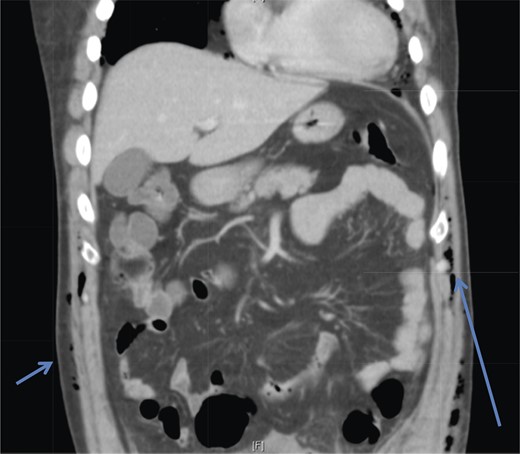

A 42-year-old male with a past medical history of hypertension was admitted for an elective TEP repair of his left inguinal hernia. Endotracheal intubation and general anesthesia were given uneventfully. The extraperitoneal space was developed with a balloon space maker, and insufflation of carbon dioxide at a maximum pressure of 12 mmHg was performed. Intraoperatively, a large incarcerated indirect left inguinal hernia containing omentum was reduced. A Optilene mesh (10 × 12 cm) was placed and tacked appropriately after hernia reduction. There were no obvious tears in the peritoneum and the total operative time was ∼90 min. No elevation of end-tidal CO2 was noted during the surgery and the patient was extubated successfully. The patient subsequently complained of left-sided chest pain on the same night of the surgery. He did not have abdominal pain. He had subcutaneous crepitus extending from the left groin to the left chest. His cardiac enzymes were negative and his electrocardiography revealed a sinus rhythm with no acute ischemic changes. A plain radiograph of the chest showed a sliver of lucency in the mediastinum suspicious for pneumomediastinum, with no obvious pneumoperitoneum or pneumothorax seen (Fig. 1). Computed tomographic (CT) imaging of the thorax and abdomen confirmed the radiograph finding of pneumomediastinum and diffuse subcutaneous emphysema tracking along the abdominal muscles bilaterally, as well as a small amount of free air and stranding in the left posterior pararenal space (Figs 2–4). The patient was treated conservatively with oral analgesia and supplemental oxygen. His chest pain resolved by the third postoperative day and he was discharged well. He was advised to avoid air travel for 1 month. He was reviewed in clinic at the 1-week and 1-month intervals and did not report any further chest pain or respiratory symptoms. His operation site healed well and he remained recurrence free.

Coronal section CT abdomen scan demonstrates tracking of subcutaneous emphysema (arrowheads).